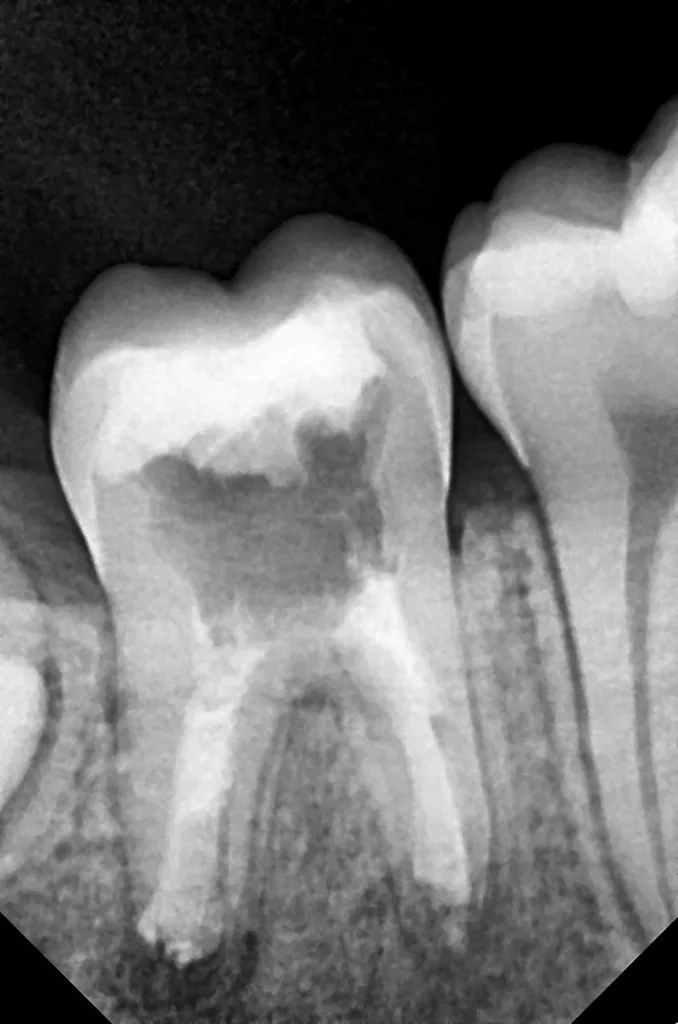

Bei routinemäßigen Röntgenkontrollen ergeben sich manchmal Zufallsbefunde unklarer Genese. So stellt sich beispielsweise bei der Betrachtung der Abbildung 1 die Frage, wie sich ein Zahnhartsubstanzdefekt so schnell entwickeln konnte. Ein weiteres Röntgenbild (Abb. 2), das vor dem Zahndurchbruch aufgenommen wurde, zeigt jedoch, dass es sich in diesem Fall nicht um Karies, sondern um die sogenannte präeruptive intrakoronale Resorption (PEIR) handelt. Für diesen Befund finden sich in der Fachliteratur auch noch andere Bezeichnungen wie „idiopathic external resorption of unerupted permanent teeth“ [1], „intra-follicular caries“ [2], „radiolucent lesions resembling caries“ [3], „occult caries“ [ 4] oder „pre-eruptive caries“ [5].

V. Slabkovskyi, O. LiutikovJahr vor dem Durchbruch des Zahnes 36.

Das fünfjährige Mädchen stellte sich 2017 zur jährlichen Routinekontrolle vor. Im Rahmen der Untersuchung wurden Röntgenaufnahmen der Milchmolaren gemacht (Abb. 2). Der klinische und radiologische Befund der vor uns früher gelegten Kompositfüllungen war gut, es wurde allerdings eine PEIR an den noch nicht durchgebrochenen ersten bleibenden Molaren festgestellt (Abb. 2). Den Eltern wurde empfohlen, sich unverzüglich bei Beginn des Durchbruchs der ersten Molaren erneut zur Behandlung vorzustellen. Ein Jahr später erschien die junge Patientin schmerzfrei zur Kontrolle. Der Zahn 36 war noch teilweise mit Gingiva bedeckt. Auf einer neuen Röntgenaufnahme (Abb. 1) wurde die PEIR-Läsion mit unveränderter Größe in pulpanahen Bereichen bestätigt (Grad 3 der Läsion nach Seow). Der Zahnschmelz sah intakt aus, es konnte kein pathologischer periapikaler Befund bei den noch nicht ausgewachsenen Zahnwurzeln festgestellt werden. Daraufhin wurden die verschiedenen Behandlungsmöglichkeiten von Fissurenversiegelung bis Vitalerhaltung der Zahnpulpa mit den Eltern des Kindes besprochen.